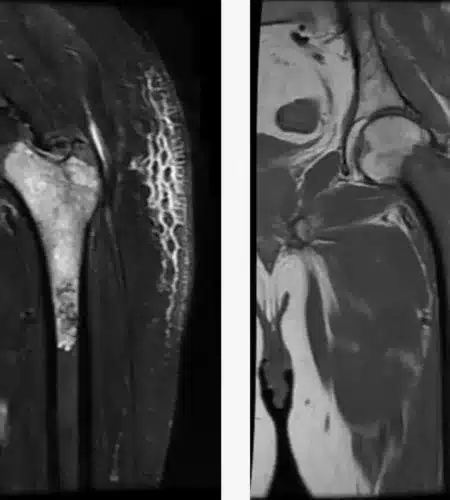

Not anymore. With advancements in technology and “Limb Salvage Surgery,” roughly 90-95% of patients can save their limbs. We remove the tumor and reconstruct the bone using metal implants or bone grafts, preserving both the appearance and function of the limb. For more details visit Dr. Pradeep.